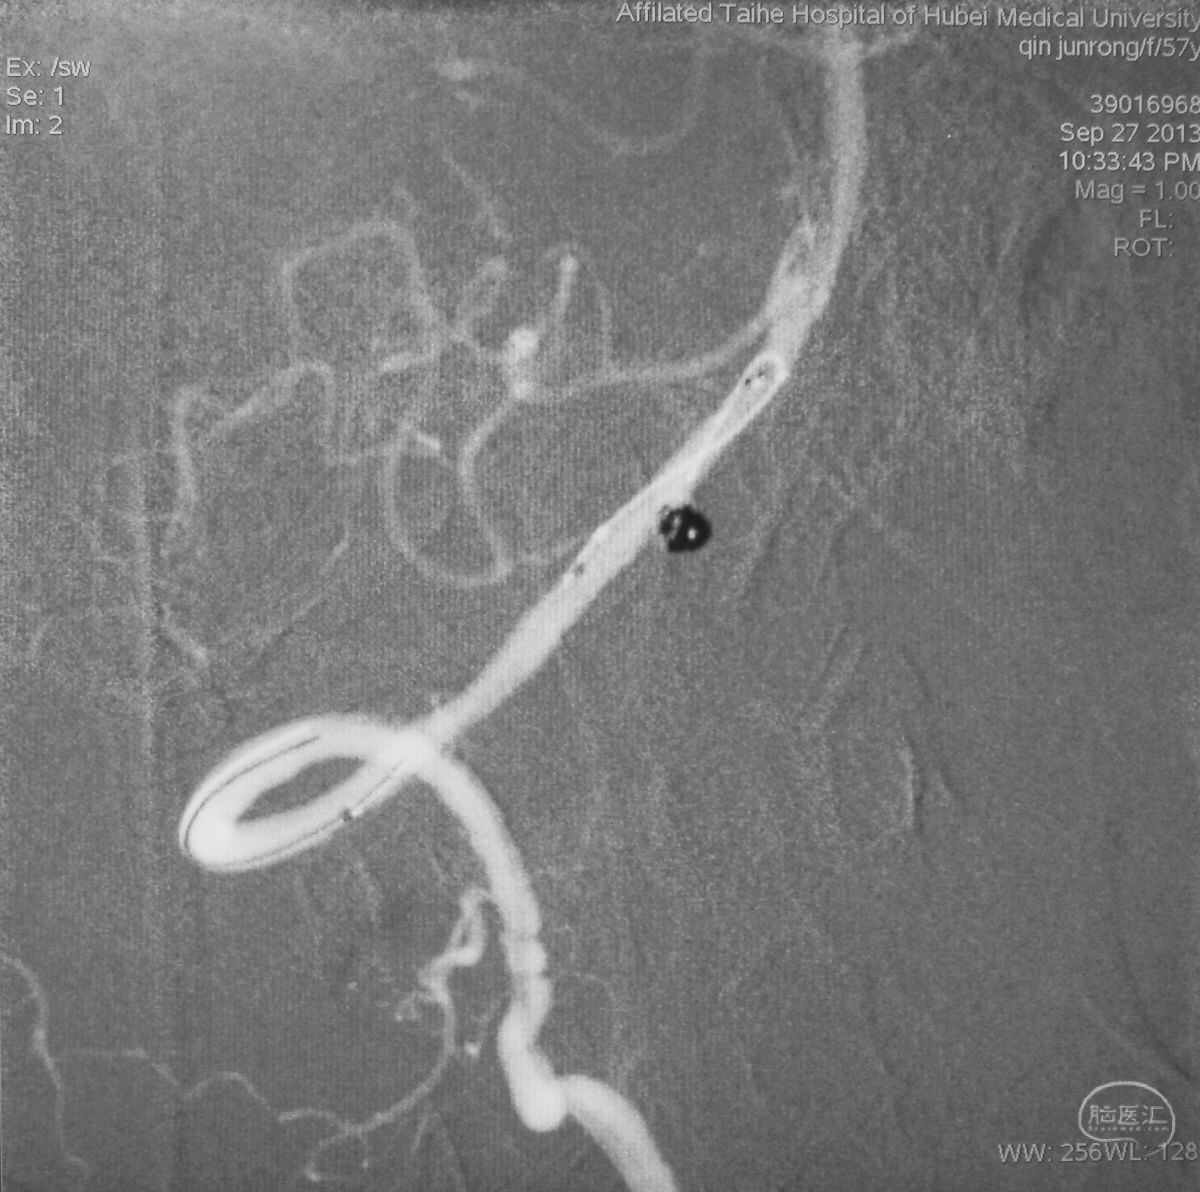

病例二,右侧椎动脉V4段夹层动脉瘤,以头痛入院,21个月前有SAH史。

右椎动脉造影三维重建

Echelon 10微导管头无论塑成C形还是S形,均无法稳定于动脉瘤腔内,遂使用回马枪技术,使微导管成襻通过,管头折返入瘤腔。

跨瘤颈释放Solitaire 4×20支架(蓝线),压住微导管(红线),在支架保护下经返折的微导管送入弹簧圈填塞瘤腔。